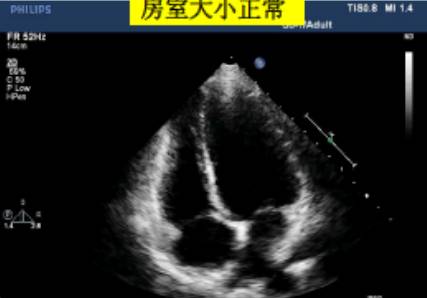

左心室正常值范围——

可用目测方法对定量数据进行反复核查。